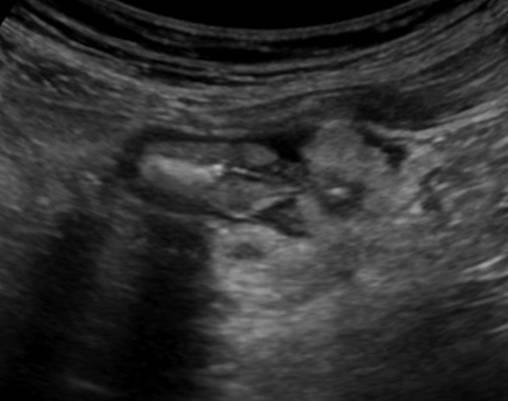

Viêm túi thừa

» Thông tin: Nam giới – 66 tuổi.

» Lâm sàng: Đau hố chậu trái / Sốt.